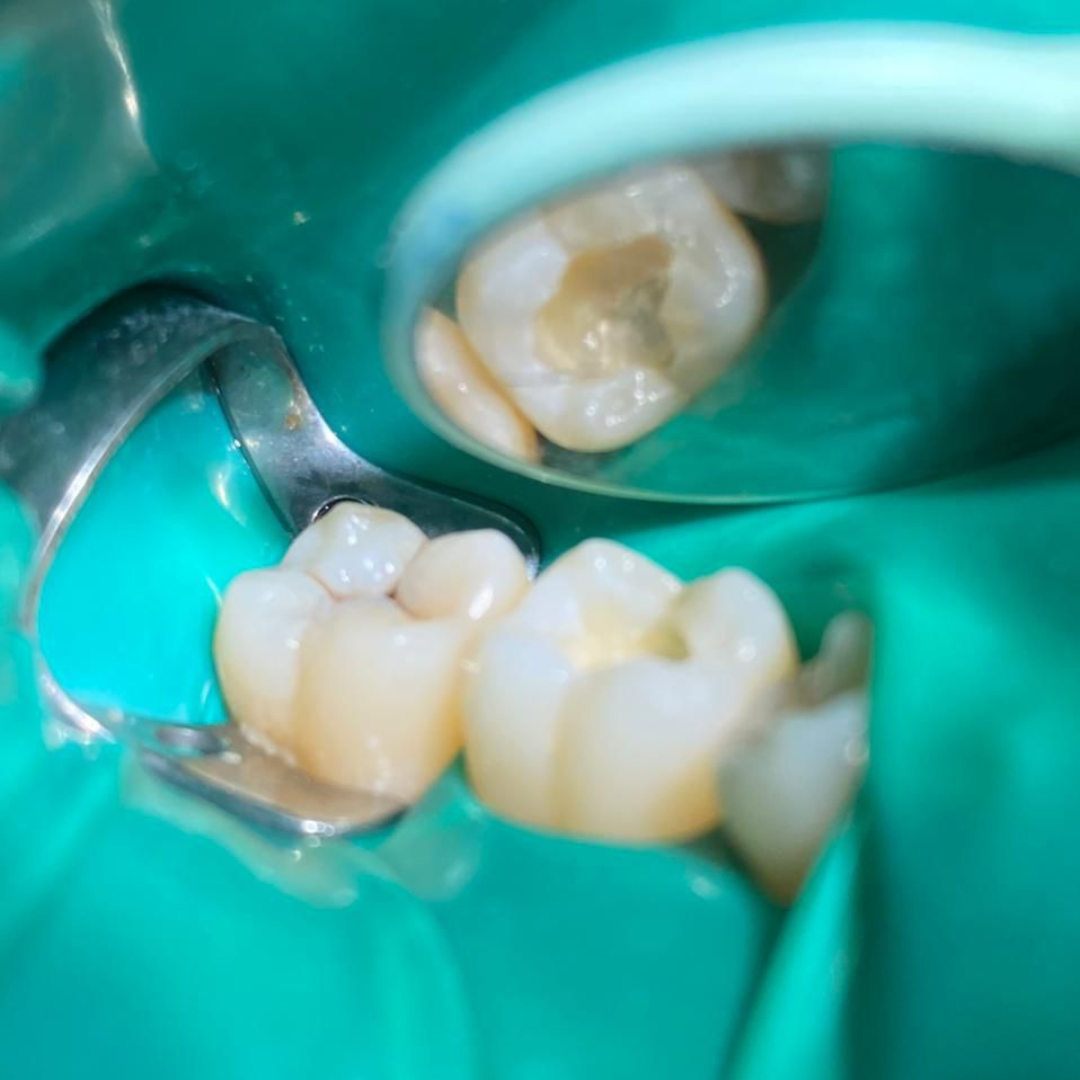

Throughout my studies, I immersed myself in learning, not just from books, but through hands-on experience at a local dental clinic. I spent countless hours there, treating patients and gaining invaluable practical skills. The joy and relief I saw in their eyes after each session were my greatest rewards. My humility and dedication earned me the love and respect of everyone around me.